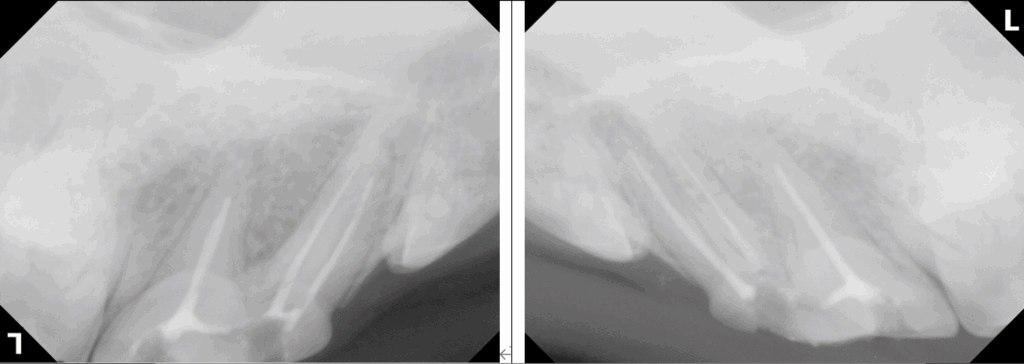

両側の露髄を伴う歯の破折の症例の紹介です。

右が露髄を伴う歯冠破折、左が露髄を伴う歯冠歯根破折です。

どちらも時間が経っているので、保存修復するには抜髄根管充填が必要です。

このような場合、抜髄根管充填と歯冠修復にそれなりに時間がかかるので少なくとも2回に分けて全身麻酔をかけて保存修復するのが一般的です。(当院でもかつてはそうでした)

今ではこのような複数歯の修復でも1日で処置することが可能なことも増えてきました。